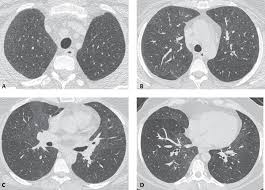

Interstitial lung disease results in six distinct radiologic patterns of abnormality. Interstitial lung disease ILD drug-induced interstitial lung disease. We describe demographic radiologic histopathologic and molecular features and p16 expression in patients with telomeres 10th percentile shortened telomeres and compare them to patients with telomere length 10th percentile.

Morphologic classifications of lung conditions diffuse interstitial lung diseases in particular have been undertaken both at the microscopic pathologic patterns and gross radiographic or thin-section computed tomographic CT patterns level. Reticular nodular high and low attenuation table. The lung interstitium is the space where the air sacs called alveoli come in contact with connective tissue and blood vessels to exchange oxygen and carbon dioxide.

In ILDs scarring damages tissues in or around the lungs air sacs and airways. On HRCT there are four patterns.

Lymphoid interstitial pneumonia LIP. IIPs include seven entities. Most of our knowledge about imaging findings in interstitial lung disease comes from HRCT. Radiographic evidence of interstitial fibrosis consisting of a reticular pattern that involves mainly the lower lung zones is seen in only about 3 of patients who have systemic lupus erythematosus. The histologic pattern aswell as the HRCT findings in AIP are indistinguishable from acute respiratory distress syndrome ARDS. Diseases that radiographically appear to involve the terminal airspaces or alveoli and those that appear to involve the interstitium. Although rare childhood ILD chILD is associated with significant morbidity and mortality most notably in conditions.